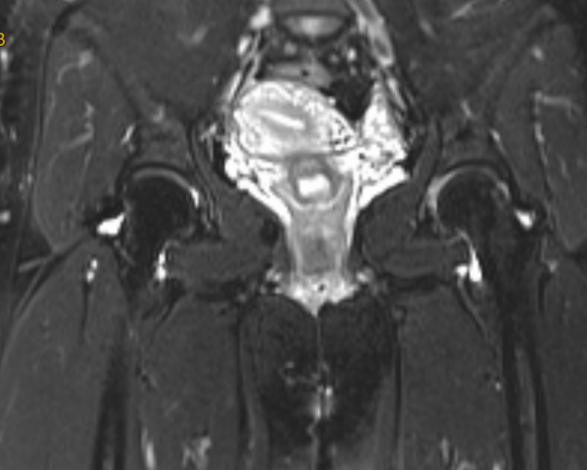

为求彻底治疗,她来到我院关节运动医学科就诊。入院后,关节运动医学团队详细查体,并完善髋关节 X 线、MRI等精准检查,结合症状与影像资料,明确诊断:髋关节撞击综合征、髋关节盂唇损伤。

该病常伴随盂唇损伤,长期拖延会加重疼痛、加速关节退变。经充分评估与沟通,关节运动医学团队为王女士制定了微创、精准、快速康复的手术方案:关节镜下髋关节撞击股骨颈成形 + 盂唇修复术。经过术前检查,无手术禁忌,手术顺利开展,全程用时不到 1 小时。